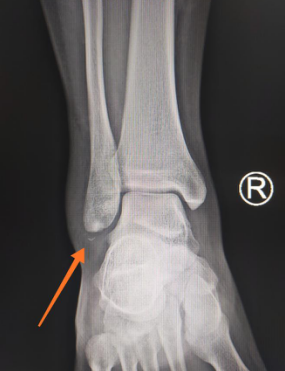

足踝科二病区周祥国医师接诊,给小夏进行了仔细检查,检查结果为右外踝骨折,右外踝关节侧副韧带断裂。

右外踝骨折

徐明亮主任和手术团队商讨,决定对患者采用关节镜进行骨折复位、韧带修复手术。“这个部位,如果采用开放手术,需要较大的切口,不仅增大创伤,而且可能加重关节内粘连;其次,开放手术暴露的区域有限,不能观察到整个关节腔,不能同时处理关节内伴随的损伤。”相较开放手术而言,踝关节镜手术具有创伤小、恢复时间短等无可比拟的优势。